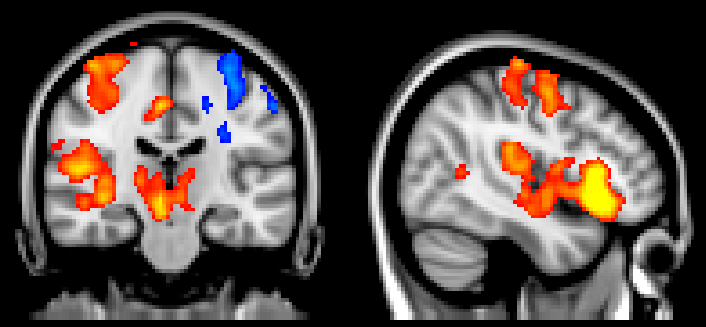

Students have the opportunity to learn a wide variety of research techniques. In addition to a variety of equipment available in faculty labs, the Psychology department EEG Neuroscience laboratory has a BioSemi 64-channel ERP system, and an EyeLink system for conducting eye tracking and pupillometry research. Faculty also conduct fMRI research at Pennington Biomedical Center’s brain imaging facility.